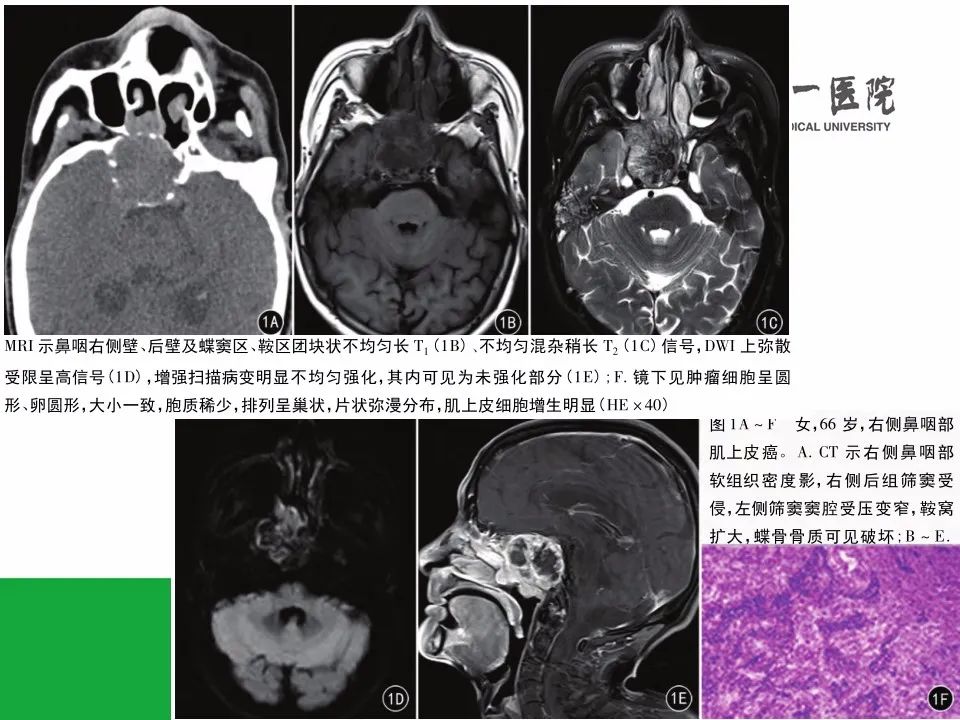

【病例】鼻咽部肌上皮癌1例CT及MR影像